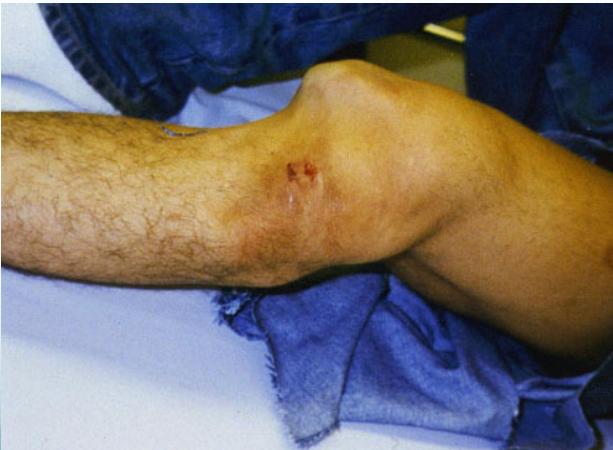

Knee (Tibiofemoral) Dislocation

- High energy: usually RTA

- Gross deformity – must examine neurovascular status

- Popliteal artery at risk

Vascular Assessment:

- Even if pulses are intact, perform angiography if there’s suspicion

- Angiography if distal pulses not felt

Management:

- Urgent reduction & vascular intervention if needed

- Then external fixation

- Reconstruction of ligaments (acute or delayed) Surgery